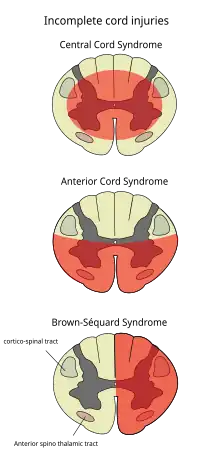

Central cord syndrome

Central cord syndrome, almost always resulting from damage to the cervical spinal cord, is characterized by weakness in the arms with relative sparing of the legs, and spared sensation in regions served by the sacral segments.[13] There is loss of sensation of pain, temperature, light touch, and pressure below the level of injury.[80] The spinal tracts that serve the arms are more affected due to their central location in the spinal cord, while the corticospinal fibers destined for the legs are spared due to their more external location.[80] The most common of the incomplete SCI syndromes, central cord syndrome usually results from neck hyperextension in older people with spinal stenosis. In younger people, it most commonly results from neck flexion.[81] The most common causes are falls and vehicle accidents; however other possible causes include spinal stenosis and impingement on the spinal cord by a tumor or vertebral disk.[82]

Anterior cord syndrome

Anterior cord syndrome, due to damage to the front portion of the spinal cord or reduction in the blood supply from the anterior spinal artery, can be caused by fractures or dislocations of vertebrae or herniated disks.[80] Below the level of injury, motor function, pain sensation, and temperature sensation are lost, while sense of touch and proprioception (sense of position in space) remain intact.[83][81] These differences are due to the relative locations of the spinal tracts responsible for each type of function.[80]

Brown-Séquard syndrome

Brown-Séquard syndrome occurs when the spinal cord is injured on one side much more than the other.[84] It is rare for the spinal cord to be truly hemisected (severed on one side), but partial lesions due to penetrating wounds (such as gunshot or knife wounds) or fractured vertebrae or tumors are common.[85] On the ipsilateral side of the injury (same side), the body loses motor function, proprioception, and senses of vibration and touch.[84] On the contralateral (opposite side) of the injury, there is a loss of pain and temperature sensations.[82][84]